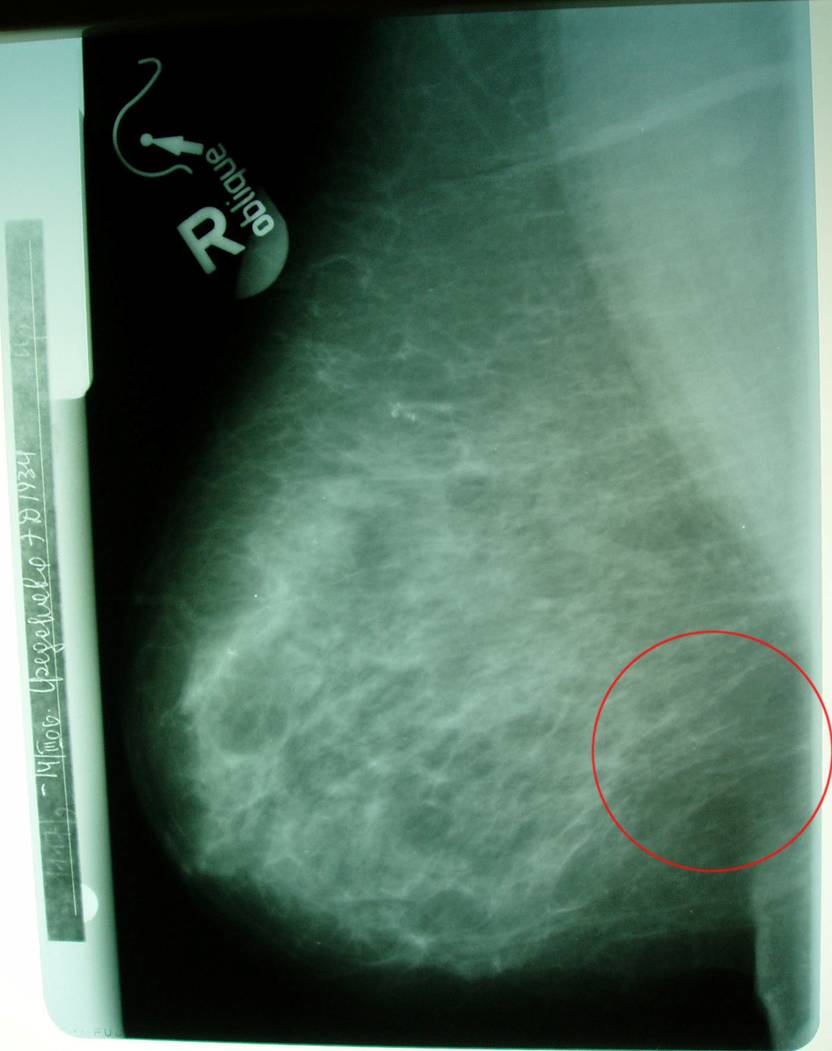

Маммограмма в динамике.

Больная раком правой молочной железы T4аN0M0. Регресс.

06.06.2005 (на момент выявления болезни)